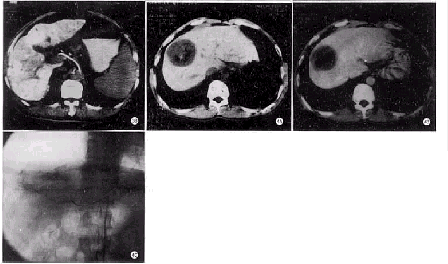

碘油组34例CT平扫显示的碘油沉积缺损区(除外肿瘤液化坏死本身不被碘油充填部分,该区可由CT值确定)与经动脉DSA所示肿瘤血管(包括残存瘤血管及侧支血供)及肿瘤染色区一致(图1)。其中12例行双期增强扫描,11例显示碘油缺损区不同程度强化,血管造影显示残存瘤血管及数量不等的侧支血供,侧支血管分别来自右膈下动脉、肠系膜上动脉、胃十二指肠动脉等;另1例CT平扫示碘油沉积缺损,呈片状低密度病灶,双期增强扫描示缺损低密度区未见明显强化。腹腔动脉造影示脾动脉、胃左动脉显影,肝总动脉及其各级分支未显影,行肠系膜上动脉的胰十二指肠下动脉微导管造影见肝总动脉及其各级分支显影,脾动脉及腹腔动脉淡薄显影,碘油缺损低密度区见少许肿瘤血管,染色淡薄(图2)。另3例CT平扫碘油沉积良好,无明显缺损,余肝实质未见异常密度影,但血管造影发现新病灶,后经导管CTA扫描证实(图3)。

微球组7例,CT平扫示瘤体不同程度缩小,中心见片状液化及气化坏死密度改变,双期增强示瘤体边缘部呈不规则厚壁状强化,4例门脉期强化程度明显高于动脉期,中心坏死区无强化。血管造影显示边缘部肿瘤血管及环状染色(图4)。

图1 A.CT平扫示肝右叶肝癌栓塞术后近膈顶部碘油沉积缺损。B.血管造影示该缺损区由粗大的右膈下动脉供血 图2 A.CT扫描示肝右叶前段缺损低密度区,增强时无明显强化。B.腹腔动脉造影时肝总动脉及其分支不显影,脾动脉及胃左动脉显影。C.肠系膜上动脉胰十二指肠下动脉造影时,胃十二指肠动脉、肝固有动脉及其分支、肝总动脉、脾动脉显影,提示肝动脉活瓣阻塞 图3 A.CT平扫见肝左叶碘油沉积良好,余实质未见明显低密度病灶。B.经导管CTA显示肝右叶出现3个新病灶 图4 A.肝癌白芨微球栓塞后CT平扫示中央区液化及气化坏死。B.2周后双期增强扫描静脉期边缘部明显强化,中央坏死区无强化。C.肝动脉血管造影示瘤体边缘部花环状肿瘤血管及染色,中央部未见供血动脉